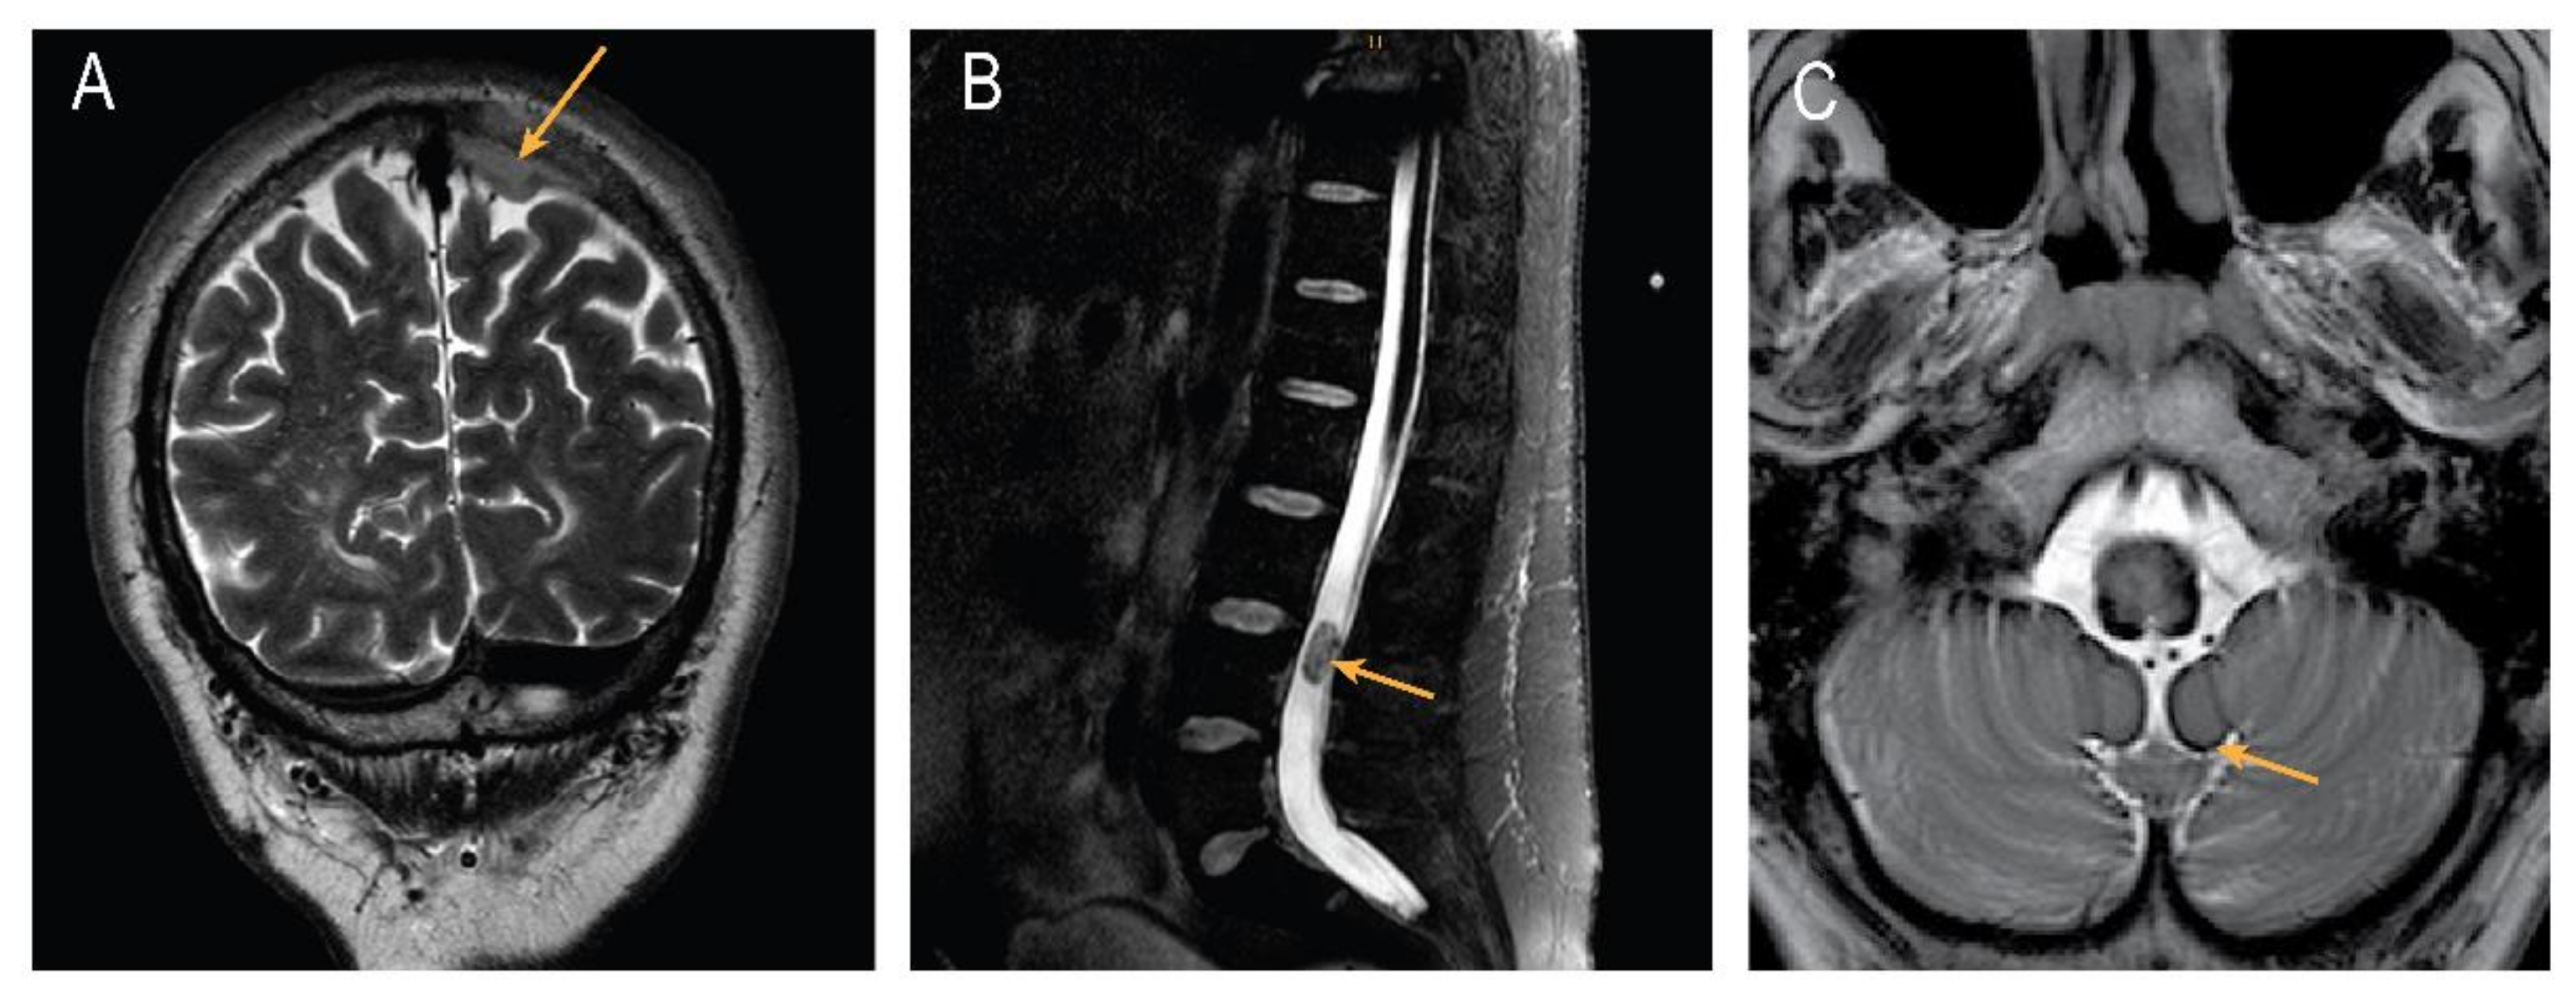

2. Case Presentation